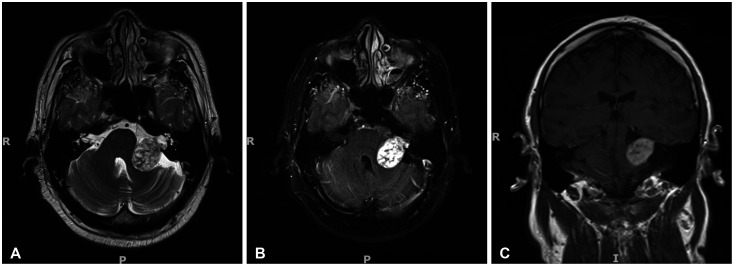

前庭分裂瘤(VS)是最常见的小脑肿瘤。对较小尺寸的 VS(30 毫米)的自然史尚未进行广泛研究,这主要是因为它们非常罕见。因此,大多数患者都会接受传统的手术治疗,而手术会带来很大的神经系统发病风险。在此,我们报告了一例 30 岁男性的巨大 VS(>40 毫米)患者,该患者自发消退。他失去随访机会长达 18 年之久,再次就诊时症状明显改善,重复造影显示肿瘤明显缩小。参考其他研究中的类似病例,我们推测大多数大型和巨型 VS 都会经历一个生长和停滞阶段,随后由于致瘤因素和消退因素之间的平衡发生变化而消退。结合新出现的分子数据,我们需要开展进一步研究,以更好地了解大型和巨型 VS 的病史,从而制定更加个性化的治疗方案。这可能包括将非手术治疗作为一种可行的选择。

Vestibular schwannomas (VSs) are the most common cerebellopontine tumors. The natural history of smaller-sized VSs (<30 mm) has been well-studied, leading to the recommendation of a "watch and wait" approach. However, large VSs (>30 mm) have not been extensively studied, mainly because of their rarity. As such, most patients are conventionally offered surgery which carries a significant risk of neurological morbidity. Here, we report a case of a giant VS (>40 mm) in a 30-year-old man who regressed spontaneously. He was lost to follow-up for 18 years and, upon re-presentation, the symptomatology drastically improved and repeat imaging demonstrated a marked reduction in tumor size. Referring to similar cases in other studies, we postulate that most large and giant VSs undergo a phase of growth and stasis, followed by regression due to shifts in the balance between tumorigenic and regressive factors. Taken together with emerging molecular data, further studies are required to better understand the history of large and giant VSs to shape more personalized treatment options. This potentially includes non-operative management as a tenable option.